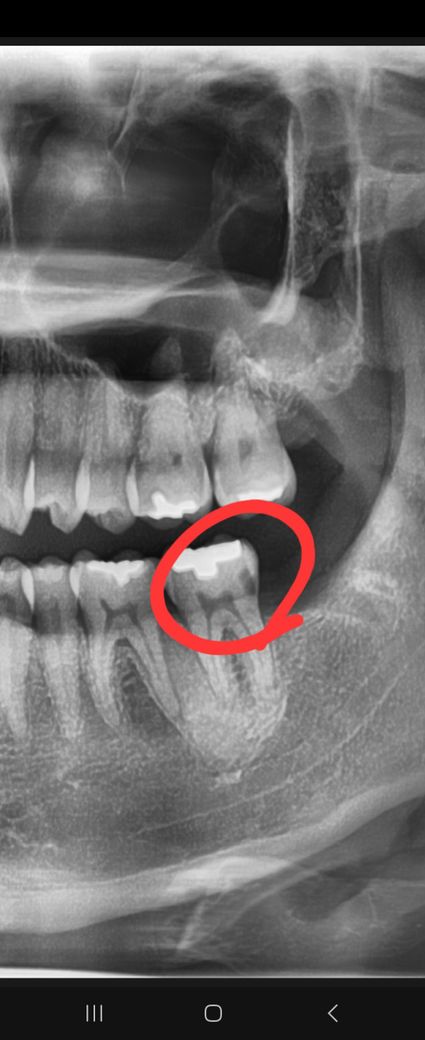

3.1개월후 직장때문에 B치과를 방문에서 오른쪽 사랑니 발치전에 x레이 찍으며 a치과에서 치료받은 어금니를 말하며(왼쪽사랑니 발치전 맞다은 곳) 왜 이곳까지 인레이 치료받지 않았냐 라고하셨습니다.( X레이상 으로 제가봐도 검게 파여있는부분이 있습니다)

4.이에 다시 A치과에 가서 인레이치료가 된것이 맞냐 라고 물으니 삭제를 최소한으로하고자했다며 f/u하면서 지켜보던지 아님 크라운을 하던지 라고하셨는데... 제생각엔 2~3개월만에 크라운얘기가 나올정도면 치료가 잘못된게 아닌지 생각이듭니다.

6.치료 전 사진

7.치료 후 사진

• 2번 째 사진

사진으로 봤을 경우에는 인레이 치료를 하고 나서도 하방에 충치가 남아있는 것으로 보이긴 합니다.

경우에 따라서 방사선 투과성이 있는 재료를 충전했을 경우에 해당 부위가 비어 있는 것처럼 보일 수도 있습니다. 충치가 내부에 남아 있다면 인레이를 제거하고 크라운 치료 등을 하는 것이 좋을 수 있습니다. 치료비 환불 등에 대한 내역은 해당 치과에 문의를 해야 정확할 것으로 생각됩니다.

현재 치료 후 사진을 봤을때 씹는면만 충치제거하고 인레이가 접착되어 있고 옆면(인접면)은 충치가 그대로 있는 것으로 보입니다.